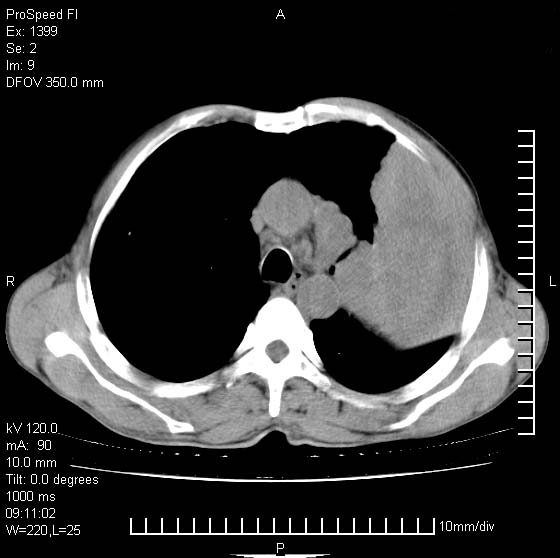

以下是引用rgsyyf在2007-1-19 11:05:00的发言:[br]左肺上叶见形态不规则巨大软组织肿块影,边缘呈分叶征,纵隔内隆突下见肿大淋巴结,右肺内另见一不规则结节影 .考虑:左肺周围性肺癌伴纵隔即右肺内转移.